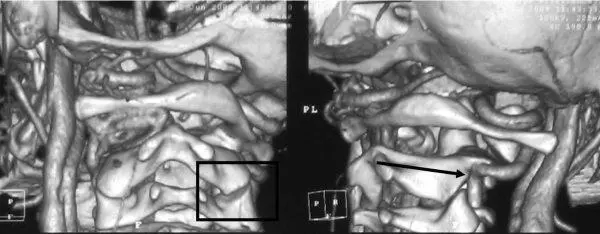

Рис. 5.15.3D КТ ангиография – асимметрия пространственного положения суставных поверхностей CII–CI. Правая позвоночная артерия деформирована